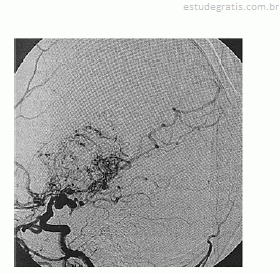

Paciente de 16 anos de idade, do sexo feminino, de asscendência japonesa, com deficits neurológicos progressivos iniciados ainda na infância, tem diagnóstico prévio de anemia falciforme. Realizou exame complementar de imagem do encéfalo, apresentado na reprodução acima. Há suspeita de doença de Moyamoya.